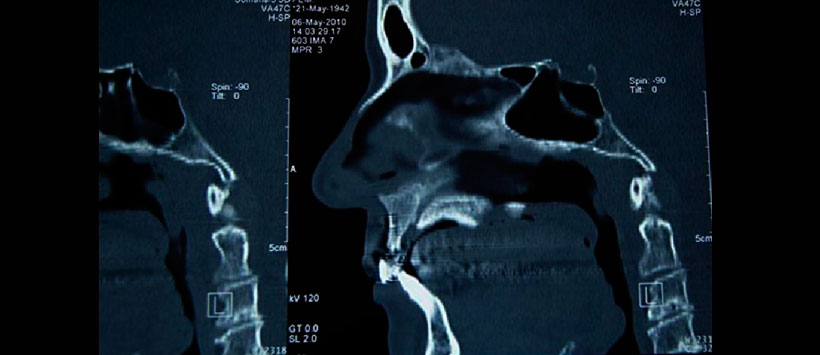

Figura 2: Tomografía computarizada (Vista axial). Prominencia de exostosis (torus) en el paladar duro)

Figura 3: Tomografía computarizada (vista lateral). Torus palatino con discontinuidad de la cortical, se aprecia zona de erosión ósea